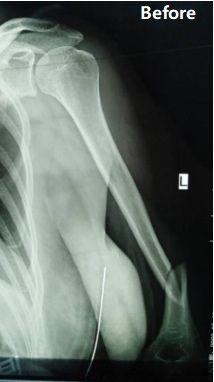

Vaka paylaşımı | orta-distal üçüncü diaphyseal humerus kırığı

Prosedür: orto-köprü sistemi ile anterior yaklaşım yoluyla minimal invaziv perkutan plaka osteosentez (mippo)

Vaka genel bakış: 48 yaşındaki bir kadın hastaya sol humeral milin orta-distalin kırılması teşhisi kondu (ao sınıflandırma: tip b1).

Cerrahi ekip, bir ortho köprü sistemi (obs) kullanarak anterior yaklaşım yoluyla minimal invaziv plaka osteosentezi (mipo) için tercih etti. Ameliyat yaklaşık 150 ml tahmini kan kaybı ve yaklaşık 8 cm insizyon uzunluğu ile 90 dakika içinde başarıyla tamamlandı.